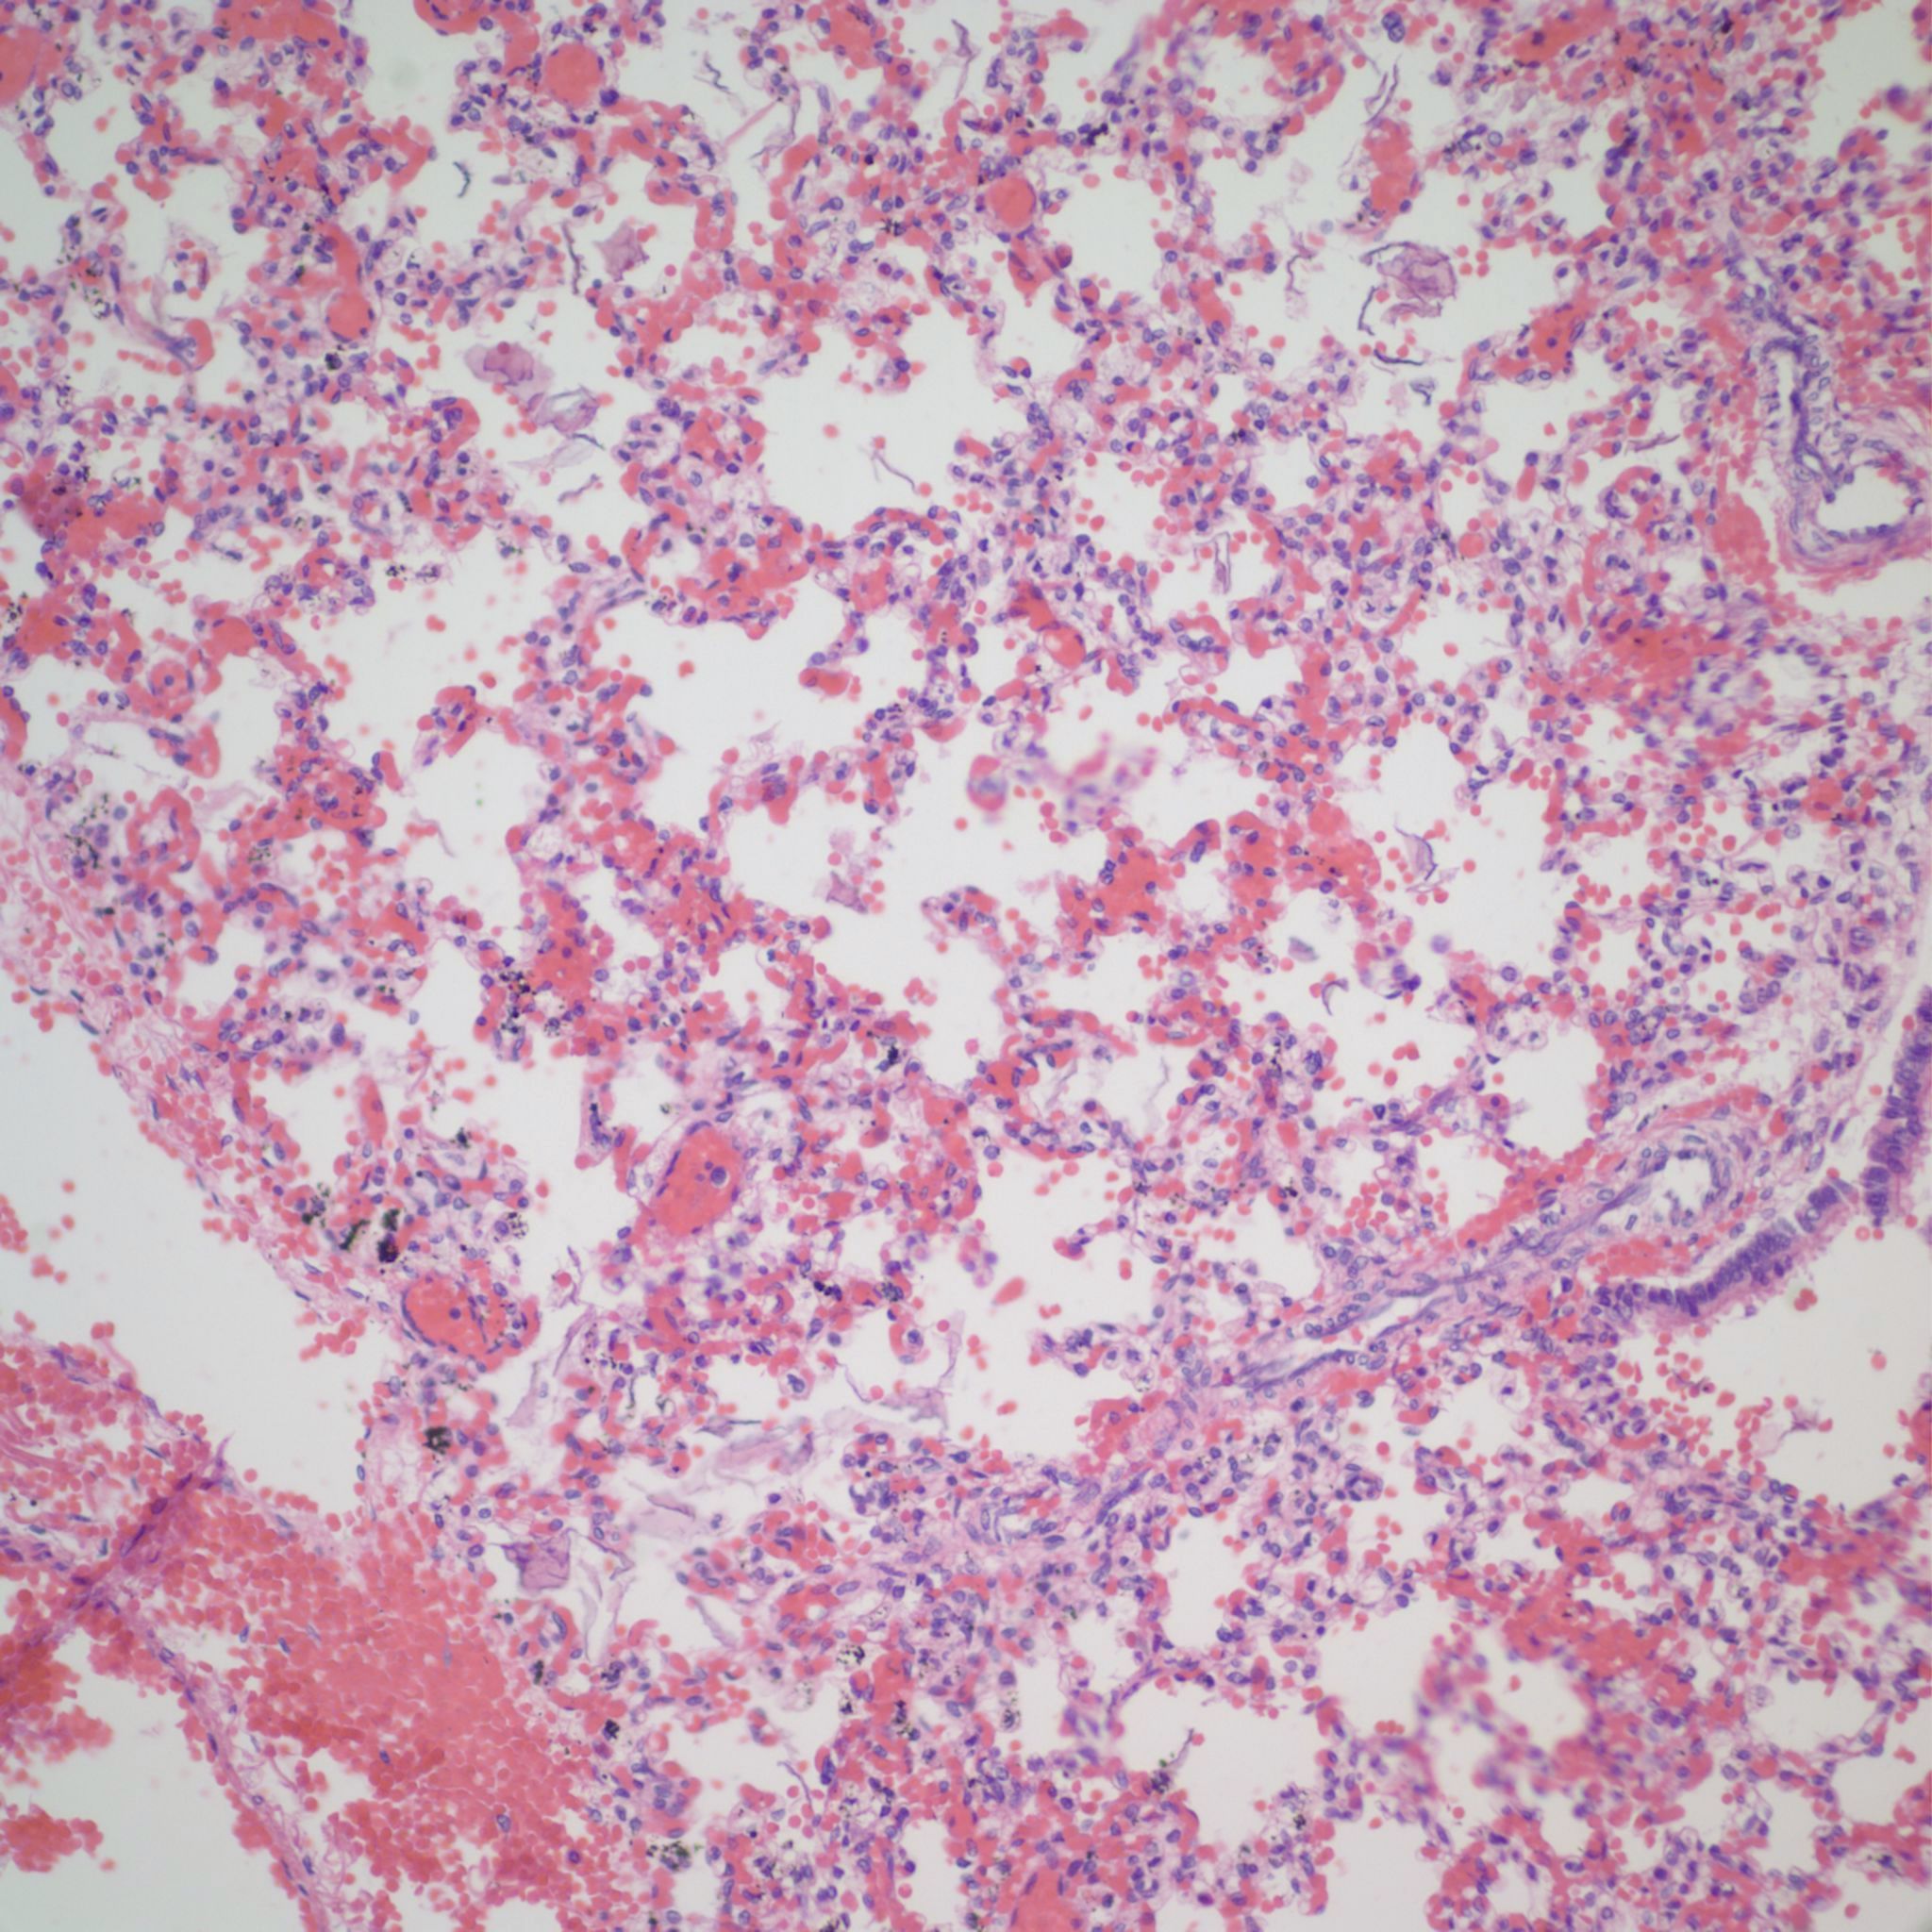

Beside hemorrhage in the visceral pleura, there may be deeper connective tissue interstitial hemorrhage in the lung. The capillaries in other areas of the lung with pleural petechiae are often engorged as well, and the rigors of gasping and pressure change may account for deeper hemorrhages (Fig 20a, b).

Focal hemorrhages may also be found in the airways usually with evidence of hemorrhages in other organs suggestive of disseminated intravascular coagulation and shock (Fig 21).